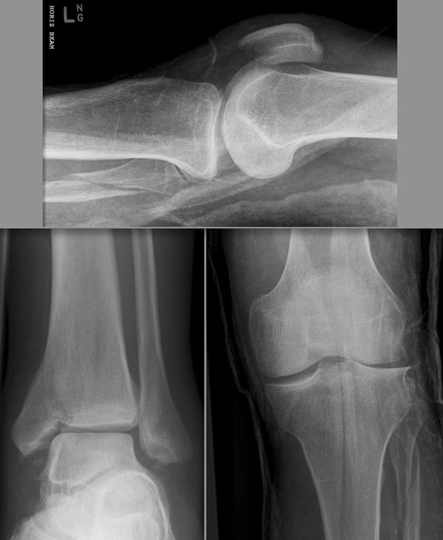

(2)三平面骨折(Triplane fracture )

即累及远端胫骨骨骺的骨折可因骨折线延入其他两个平面而变得复杂,因而称之。骨折由矢状面内的骨骺骨折,经生长板外侧面的轴位面内水平方向骨折,与冠状面内经干骺端到骨干的斜行骨折,自生长板的前侧面伸延至胫骨的后侧皮质。

三平面骨折示意图